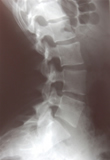

Rückenschmerzen

Als Ursache infrage kommen ein akuter Bandscheibenvorfall, aber auch Entzündungen oder Blockierung eines der kleinen Wirbelgelenke.

Verantwortlich hierfür sind meist Abnützungserscheinungen der Bandscheiben, kleinen Wirbelgelenke sowie knöchernen Strukturen der Wirbelsäule. Oft sind aber auch Narbenbildungen nach Bandscheibenoperationen die Ursache chronischer Rückenschmerzen.

Seltene Schmerzursachen stellen Entzündungen im Bereich von Wirbelkörpern oder Bandscheiben oder Tumore dar.